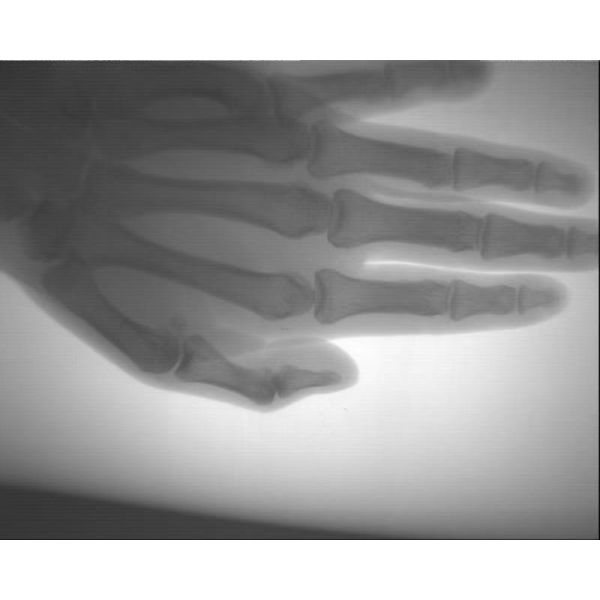

Easy Taken Portable X Ray Machine With High Definition USB / Computer Storage

1. Hospital orthopedics, hand and foot surgery, pediatrics, dental and so on

2. Fracture distal radius closed reduction, needle external fixation treatment

3. Taking Foreign body from muscle

Clear images: